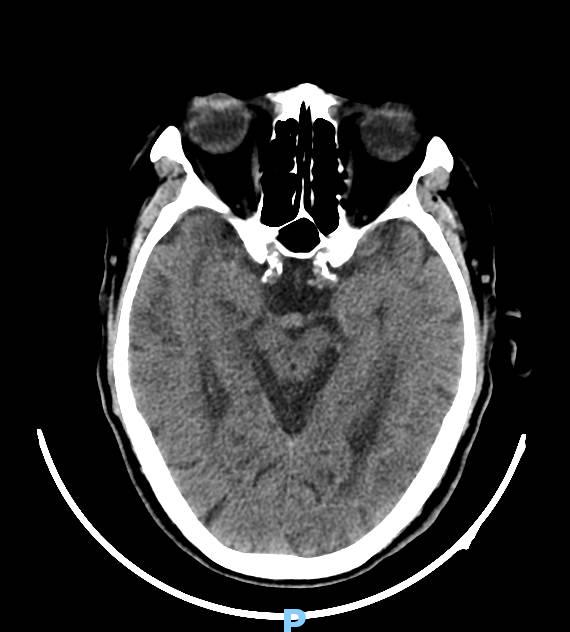

头部CT平扫

70多岁老人因“皮肤瘙痒皮疹4天伴发热2天”入急诊内科住院,经过头部CTA检查发现基底动脉末端动脉瘤,如下图